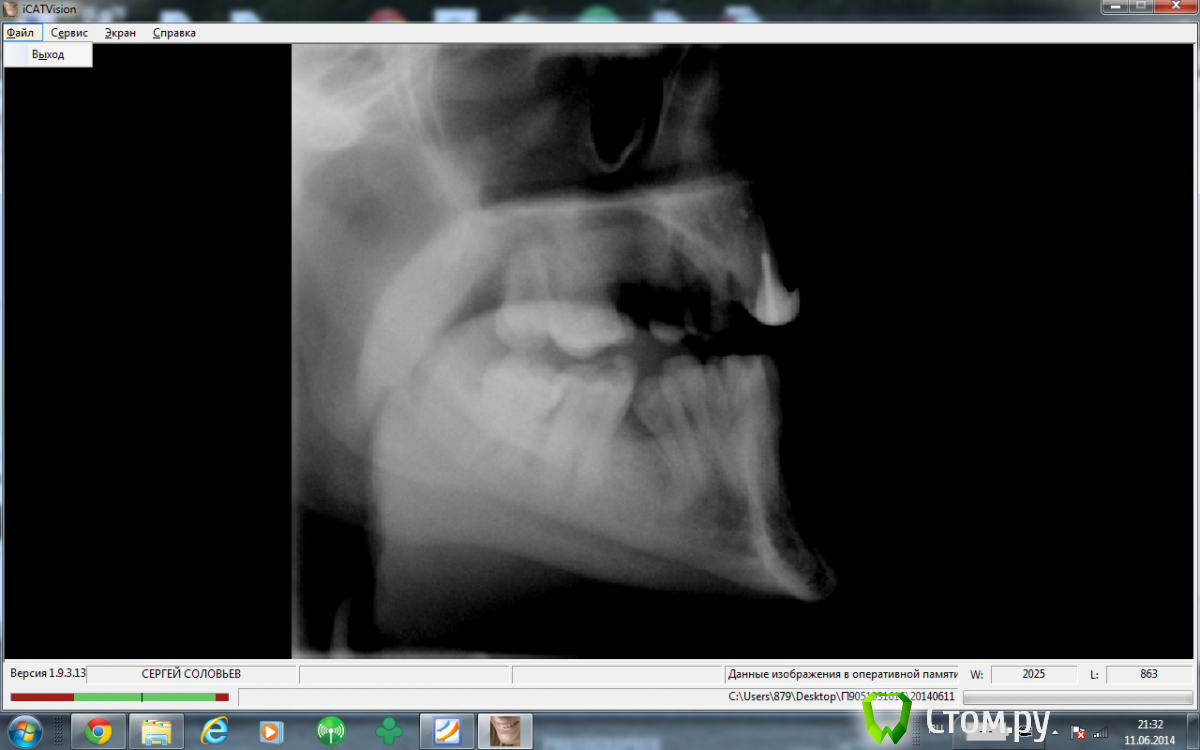

sergey765 Опубликовано 11 июня, 2014 Автор Поделиться Опубликовано 11 июня, 2014 посмотрите пожалуйста КТ. Ссылка на комментарий

sergey765 Опубликовано 11 июня, 2014 Автор Поделиться Опубликовано 11 июня, 2014 могу вам ещё снимков выложить.их довига. беспокаят меня боли после удаления .прошло 5 недель. снимки девушка лет 20 эти смотрела. сказала что у меня там инфекции дофига. типа давай я тебя на понедельник к хирургу запишу. он ранку вскроет. прочистит Ссылка на комментарий

Bier Опубликовано 11 июня, 2014 Поделиться Опубликовано 11 июня, 2014 это все не информативные кадры, в прикрепленных темах есть инструкция, выкладывайте КТ целиком, наш рентгенолог скачает и выложит срезы. 3 Ссылка на комментарий

sergey765 Опубликовано 12 июня, 2014 Автор Поделиться Опубликовано 12 июня, 2014 хорошо сейчас скидываю весь диск в рар архиве в файлообменник. люди добрые пожалуйста скачайте посмотрите. умоляю на коленях. ситуация у меня крайне серьезная. мне нужно чтобы хороший хирург посмотрел. в долгу не останусь. и если что у меня сильно там серьезное приеду к вам в клинику в москву/питер. а там что-то полюбас будет..... вчера когда делал КТ в частной клинике девочка (лет 20) смотрела, нифига вроде не поняла, сказала только у меня там инфекции полно (где там я не понял) и лунка удаленного зуба не заживает типа надо хирургу показать он вскроет прочистит т.е возможно когда мне зуб удаляли не прочистили там ничего... сейчас меня беспокоят боли в районе подбородка. самочувствие моё плохое. с кровати почти не встаю. все написано в начале данной темы.умоляю скачайте посмотрите. томограмма сделана программой iCATVision Ссылка на комментарий